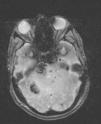

Las manifestaciones clínicas, de inicio entre 20 y 40 años, comprenden crisis epilépticas, cefalea y déficit neurológico por hemorragia cerebral o compresión. La mayoría de cavernomas se localizan supratentorialmente, aunque pueden encontrarse también en el troncoencéfalo y la médula espinal12. La resonancia magnética (RM), y en especial la secuencia ecogradiente, es la prueba más sensible para su detección. La imagen característica es en “palomita de maíz”, con núcleo reticulado bien delimitado, señal heterogénea por sangre en distintos estadios y reborde hipointenso de hemosiderina7.

Su clínica de inicio consistió en crisis comiciales en 5 (3 varones y 2 mujeres), déficit focal neurológico en 2 (varones) consistente en parestesias y monoparesia MII en un caso y ataxia con nistagmus y paresia del VI par izquierdo en otro y cefalea en una (mujer). La RM mostraba cavernomas cerebrales múltiples típicos en hemisferios cerebrales, troncoencéfalo y, en un caso, medular (fig. 2). En RM seriadas se observó aparición de nuevas lesiones y evolución de las anteriores. Cinco pacientes presentaron sangrado agudo en la RM (3 mujeres y 2 varones) en protuberancia derecha, 3 frontales izquierdas y uno en raíz de cola de caballo.